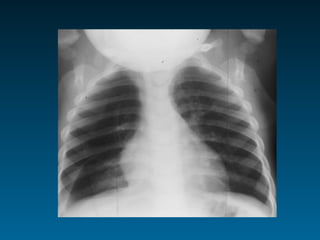

Παθολογικές διαυγάσεις παρεγχύματος

Διάχυτη Υπερέκπτυξη

βρογχιολίτιδα

ασθματική κρίση

χρονίως αλλεργικός πνεύμονας

ξένο σώμα τραχείας

συμπίεση τραχείας

κυστική ίνωση παγκρέατος

συγγενής καρδιοπάθεια